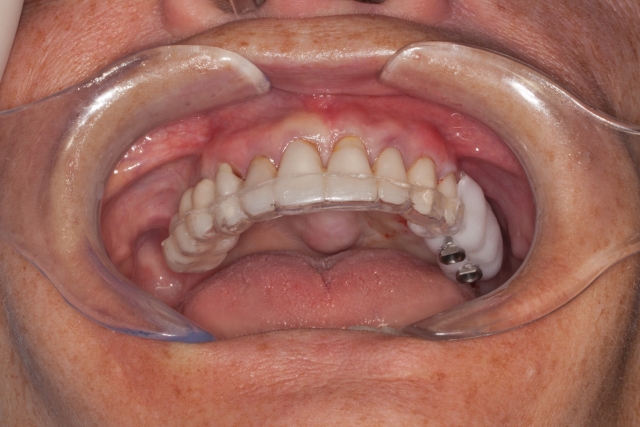

10. When tried in, the template should be solid and stable and have a “snap-fit.”

The patient can be instructed in how to insert the appliance and can take it with them if they are having the CBCT done outside of your office. The end result will give you and the surgeon a more clear understanding of potential implant positions. The hole that is drilled through the teeth will be radiolucent on the CBCT and serve as an indicator of possible implant angulation that can be corrected by the surgeon as the case is planned.